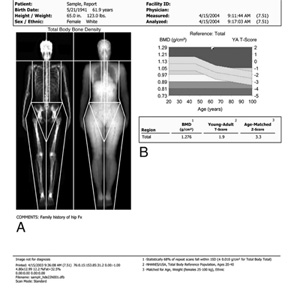

If your period becomes irregular, or, if you develop signs of menopause, such as hot flashes, talk with your doctor. You also may want to ask about bone density testing. This is a safe, painless, x-ray technique that compares your current bone density with the peak bone mass someone your same gender and ethnicity should have reached at 20 to 25 years of age.

A duel-energy x-ray absorptiometry (DXA) scan is the "gold standard" of bone mineral density testing.

Reproduced with permission from JF Sarwark, ed: Essentials of Musculoskeletal Care, ed 4. Rosemont, IL, American Academy of Orthopaedic Surgeons, 2010